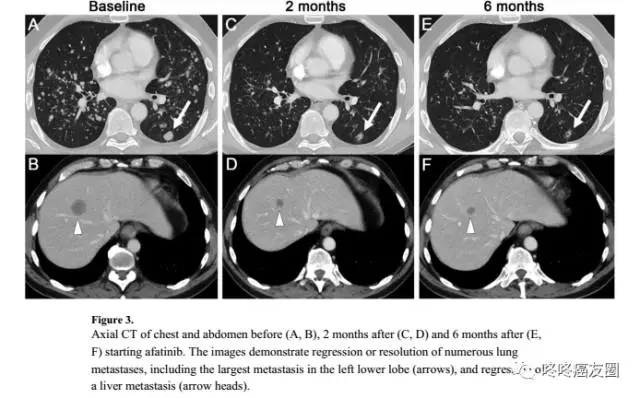

这是一个携带有HER2基因20外显子775位YVMA插入突变的病人,在接受了四五种其他药物的治疗纷纷失败以后,尝试了阿法替尼,用药2个月后,病灶就明显缩小了。